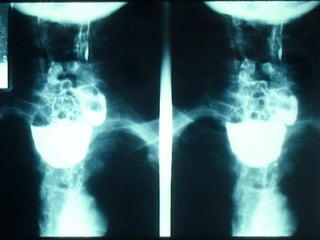

SEGD Puntos normales de estrechamiento del esófago A nivel cartílago cricoides Altura de botón aórtico Donde cruza el bronquio izquierdo El sitio donde pasa a través del diafragma

SEGD Puntos normalesde estrechamiento del esófago A nivel cartílago cricoides Altura de botón aórtico Donde cruza el bronquio izquierdo El sitio donde pasa a través del diafragma